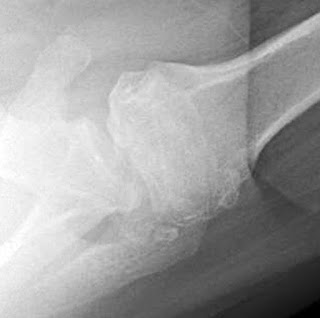

Neurotropic (Charcot) arthropathy

This condition arises in association with syringomyelia, diabetes, or other causes of joint denervation. The joint and subchondral bone are destroyed because of loss of the trophic and protective effects of its nerve supply. Cervical spine trauma might have occurred in the past, or unrecognized syringomyelia might exist. Other causes include diabetes, leprosy, syphilis, and chronic alcoholism. It has been suggested that the injection of corticosteroids might accelerate the development of this condition. The Charcot joint is characterized by functional limitation and pain (despite the denervation). Significant bone destruction and osseous debris are usually present about the joint area.

To help remember the characteristic features, we use the pneumonic of the three “d”s: “denervation, destruction and debris”. This condition can resemble infectious arthritis. The longevity of an arthroplasty performed for Charcot arthropathy may be jeopardized by the lack of protective nerve supply.